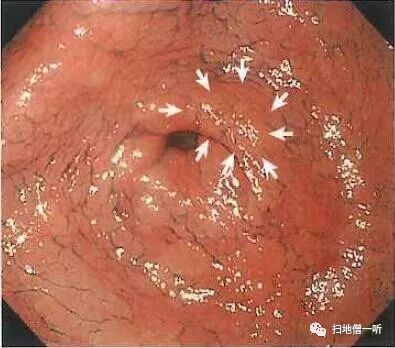

A2:隐藏于其他图片中的病变位于图11及图12

幽门后壁可见片状黄色调粘膜。

接近观察后可见区域内粘膜光泽度消失,粘膜粗糙呈颗粒感,怀疑癌,进一步行靛胭脂染色及NBI观察。

幽门后壁,O-IIc,6mm,tub1,T1a(M),UL(-)